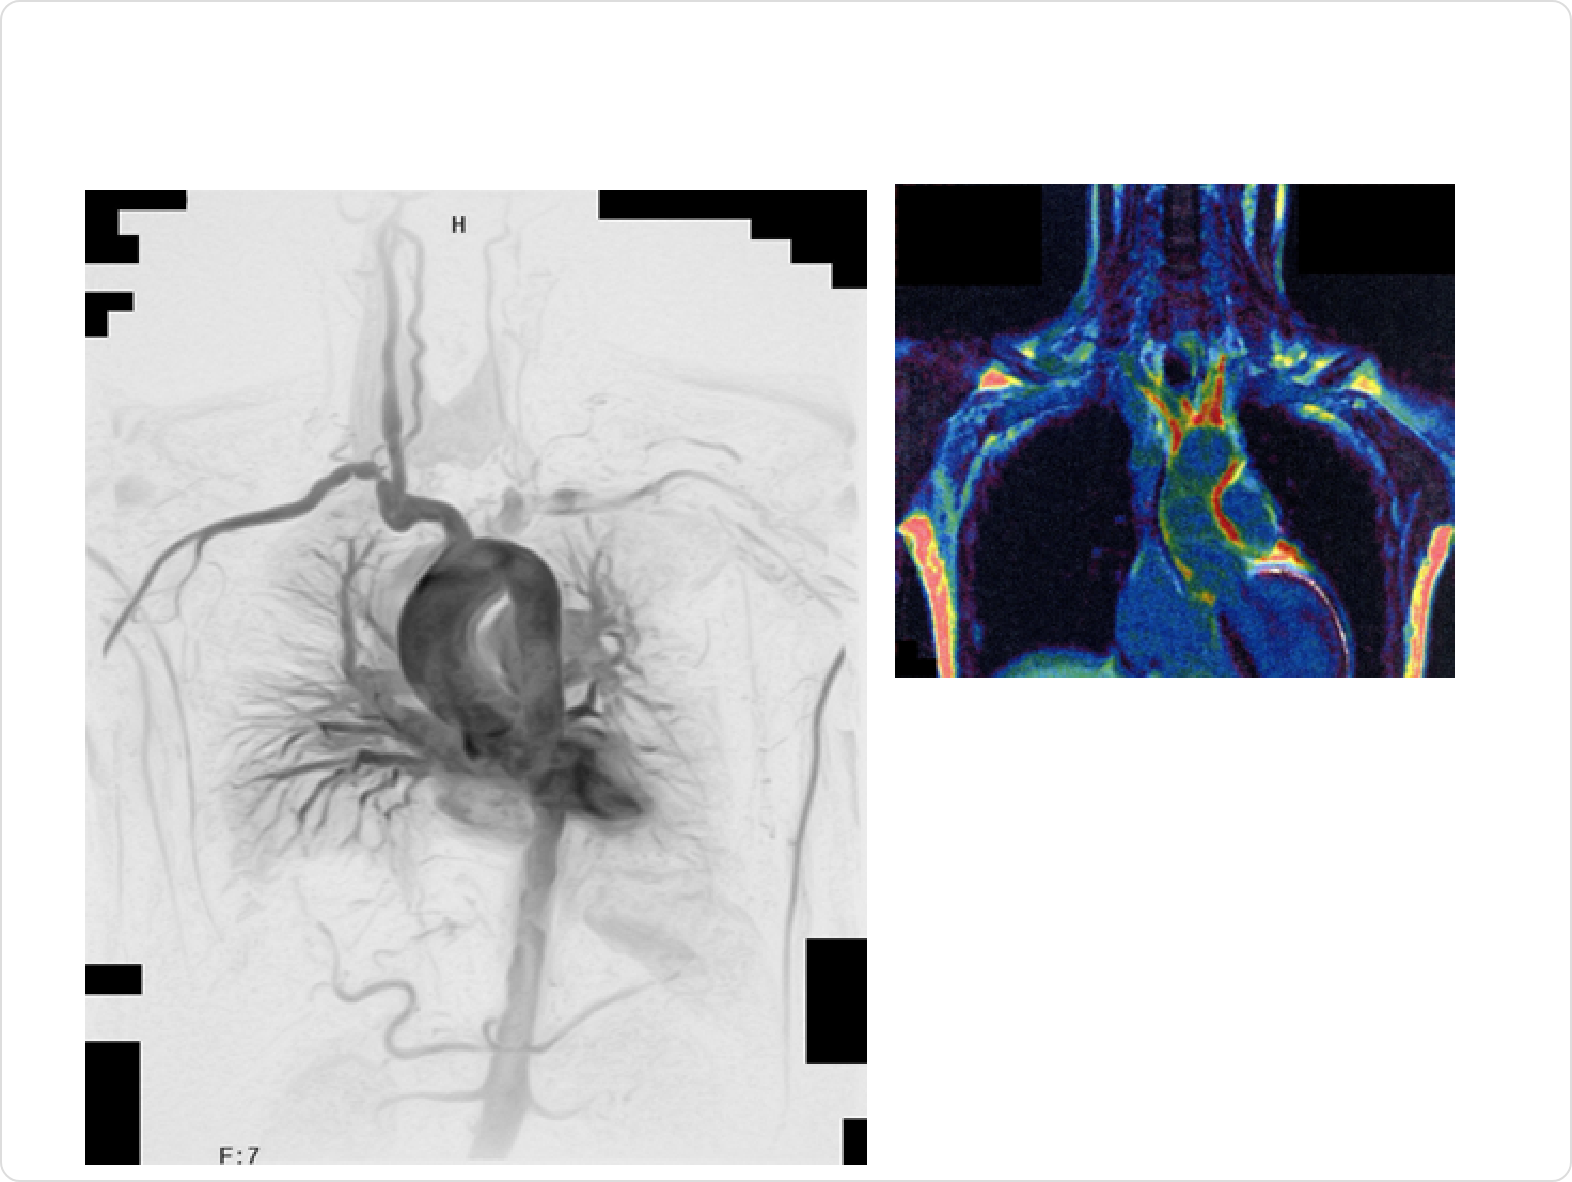

MRA

MRAは、磁気共鳴画像(MRI)を用いて、血管を中心に再構成して得られる画像です。放射線の被曝はありませんが、造影剤が必要です。撮影時間もCTより長くなります。高安動脈炎の診断、治療効果の判定、長期的な経過観察によく使われ、信頼性と安全性の高い検査です。一方で、細い血管がきれいに写らない、撮影に時間がかかるなどの欠点もあります。下の右側の画像では、大動脈の壁厚が赤く染まって見えます。

PET

PETは、造影剤が不要で、安全性の高い検査です。高安病の炎症がある血管が濃く(赤く)染まります。現在活動性の炎症があるかどうか、どの場所に炎症があるかなどを知るために用いられる、最も信頼性が高い検査です。治療効果の判定、手術前の炎症の評価などにも使われます。既に診断がついている患者さんに限り、保険診療のもとで検査が可能となりました。